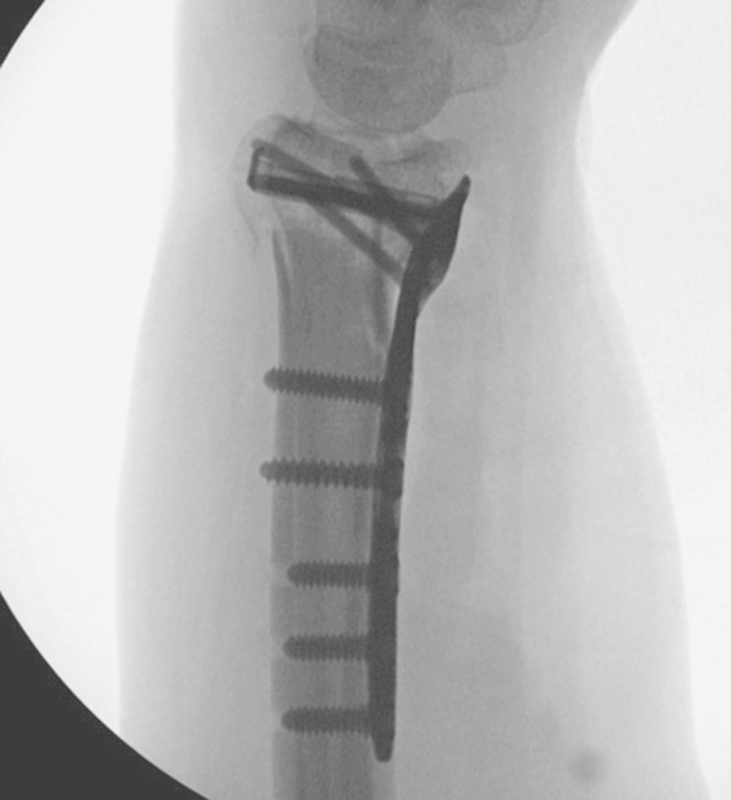

Fig. 9.

Radiograph showing placement of locking and non-locking screws into the dorsal rim buttress plate.

Fig. 10.

Posterior/anterior radiograph showing anatomic reduction of the joint surface with stable fixation of both the lunate and radial styloid fragments with a low profile of the dorsal rim plate.

Fig. 11.

Lateral radiograph showing anatomic reduction of the intra-articular distal radius.